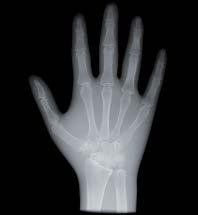

L’innovazione e la sicurezza sono due dei valori perseguiti dallo Studio Braconi a Terni, un punto di riferimento nell’ambito della radiologia 3D ortopedica grazie alla presenza del macchinario Newton 5G XL: si tratta dell’unico apparecchio nel Centro Italia che permette di eseguire una perfetta diagnostica per immagini in ortopedia e per la cervicale, oltre per le piccole articolazioni come seni paranasali, orecchie, colonna cervicale, gomito, polso, mano, ginocchio, caviglia e piede.

Nell’ambito della radiologia 3D ortopedica, il centro diagnostico utilizza il nuovissimo macchinario NewTom 5G XL, in grado di individuare con la massima precisione la presenza di fratture o lussazioni delle articolazioni, controllare la corretta guarigione di una frattura, valutare una lesione o una ferita causata da infezione, artrite o crescita anormale dell’osso.

Se con la radiologia tradizionale era necessario eseguire scansioni multiple, la novità introdotta dal macchinario NewTom 5G XL risiede nella capacità di fornire immagini ad alta risoluzione in un’unica scansione, mostrando nitidamente i dettagli delle articolazioni degli arti superiori e inferiori. Inoltre, a differenza della tecnologia 2D, la radiologia 3D ortopedica permette di individuare immediatamente alcune patologie come quella del metatarso, la quale richiede un allineamento visivo dedicato o una diagnosi delle micro fratture ossee.